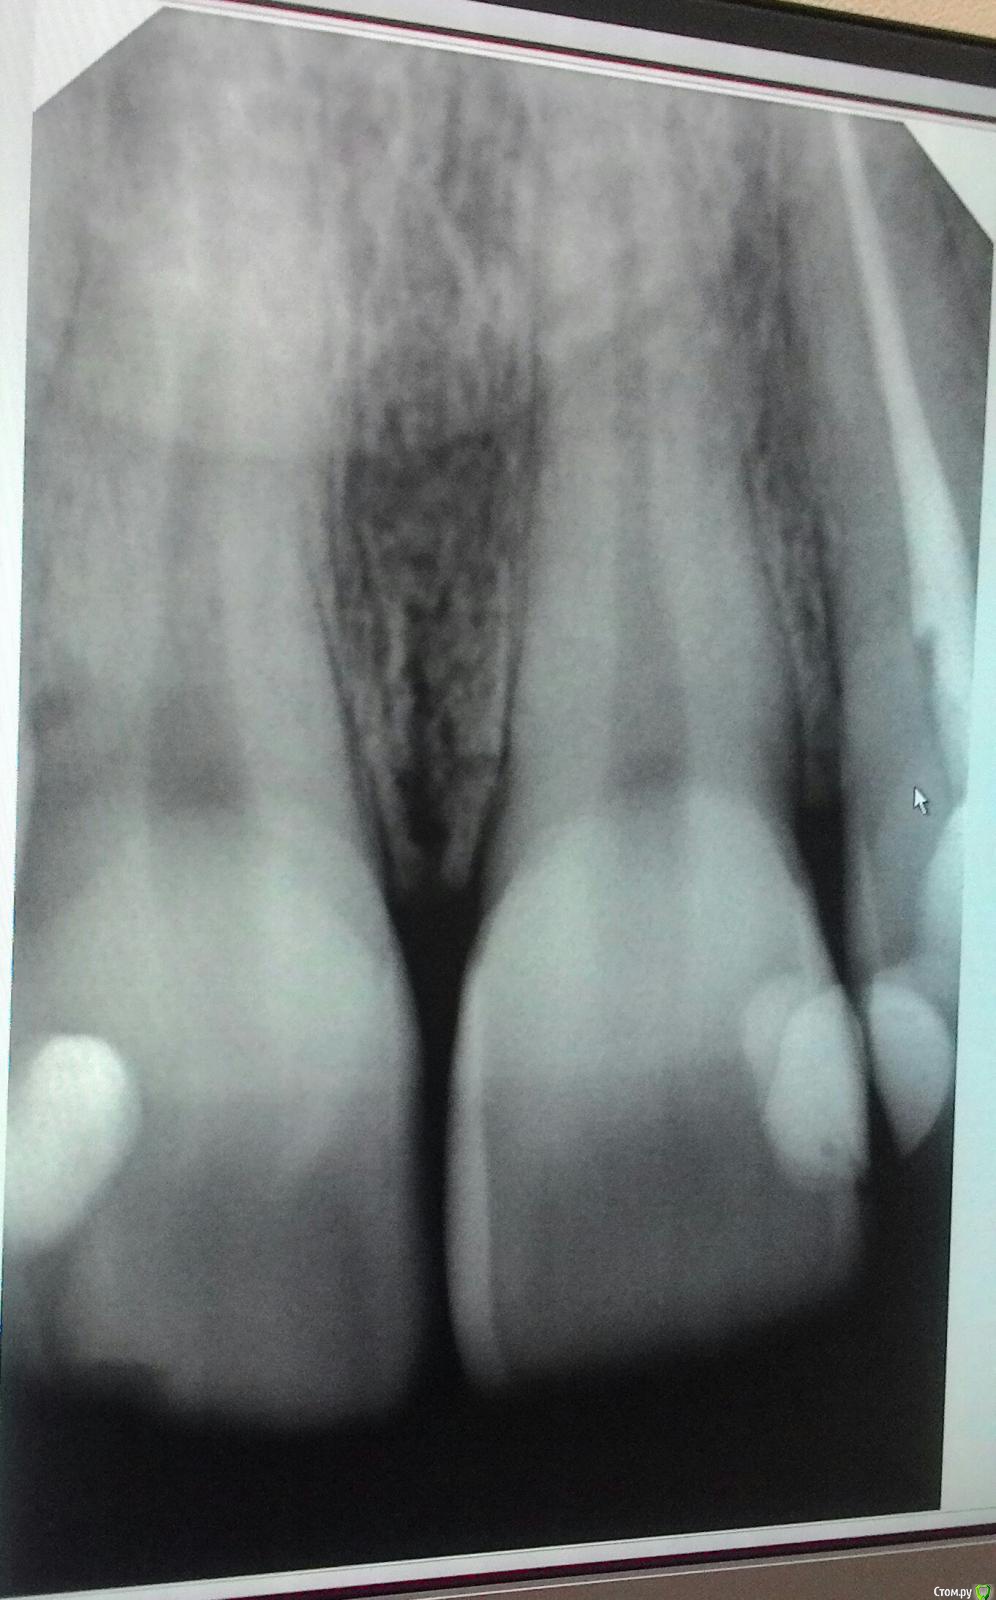

anaG2011 Опубликовано 2 июля, 2018 Поделиться Опубликовано 2 июля, 2018 (изменено) Здравствуйте, уважаемые врачи!Скажите, пожалуйста, нужно ли лечить 11 зуб (центральный правый резец - на фото он слева)? Стоит пломба 2001г. на небной поверхности (сзади). Зуб не беспокоит. Была на осмотре у двух врачей по поводу 11 зуба:1 мнение: Пломба нормальная, если и есть вторичный кариес, то он минимален (даже больше похоже на пигментацию).Рекомендует пока наблюдение 6 месяцев.2 мнение: однозначно лечить сейчас, пока процесс не дошел до пульпы. 22 зуб (левый боковой резец) депульпирован в 2001г. Зуб не беспокоит.12 зуб (правый боковой резец) пломба 2001г. Зуб не беспокоит. Буду благодарна за ваши рекомендации. Изменено 2 июля, 2018 пользователем anaG2011 Ссылка на комментарий

anaG2011 Опубликовано 2 июля, 2018 Автор Поделиться Опубликовано 2 июля, 2018 Добрый вечер !Я не совсем поняла Ваш ответ. Уточню: 12 зуба (правого бокового резца) на снимке нет.11 зуб на снимке расположен слева, затем 21 и самый правый на снимке 22 (депульпирован). Эти зубы лечила в 2001г. Они меня не беспокоят.Хочу понять, есть ли показания лечить. Сначала была в платной стоматологии (мнение 2) - сказали лечить сейчас.Потом в бесплатной городской поликлинике (мнение 1) - пломбы нормальные, наблюдаем полгода. Буду признательна, если Вы поясните Ваше мнение. Спасибо Ссылка на комментарий

anaG2011 Опубликовано 5 июля, 2018 Автор Поделиться Опубликовано 5 июля, 2018 (изменено) Здравствуйте! Дополню вопрос более четкими прицельными рентгеновскими снимками. центральные резцы и 22 зуб:https://c.radikal.ru/c35/1807/59/867599037145.jpg 12 зуб и частично 11 зуб:https://d.radikal.ru/d26/1807/85/5ca9d97b2ed0.jpg Буду благодарна за рекомендации. Изменено 5 июля, 2018 пользователем anaG2011 Ссылка на комментарий

DmitrySH Опубликовано 5 июля, 2018 Поделиться Опубликовано 5 июля, 2018 12, 11, 22 Есть дефекты пломб, лучше переделать. Ссылка на комментарий